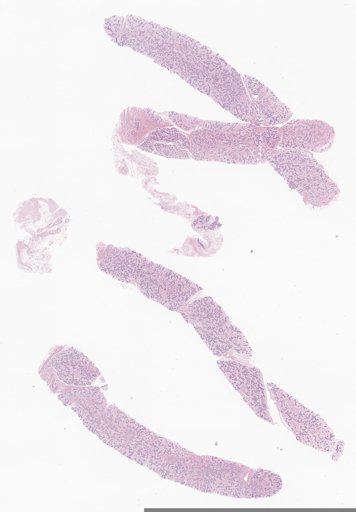

2492 Breast Biopsies.

| Staining |

Hematoxylin and eosin stain method |

| Number of WSIs | 2492 |

| Number of cases | 1046 |

| Center name | Institute of Pathology, Technical University of Munich |